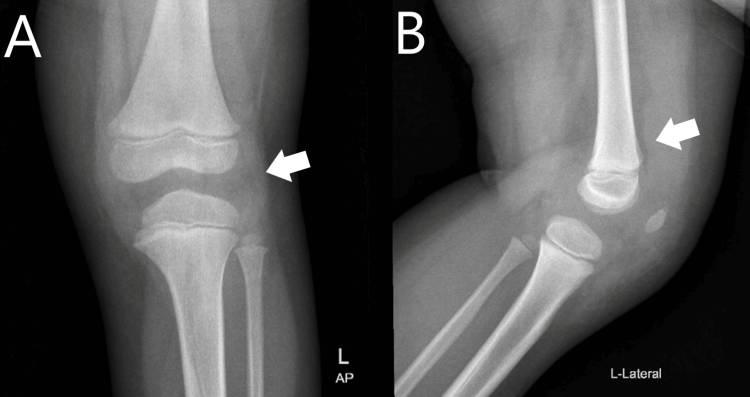

经检查,左膝触痛,有明显红斑和发热。患者只有0-90度的活动范围,运动疼痛。实验室评估显示,白细胞(WBC)计数正常,但炎症标志物较高。对左膝进行了X光检查(图1),结果显示关节周围软组织肿胀,髌上脂肪垫膨隆,指向关节积液。超声(US)还发现膝关节周围软组织肿胀,髌上囊扩张,滑膜增厚,液体少(图2)。

图1 左膝的前后视图(A)和侧视图(B),箭头显示关节周围软组织肿胀(A中的箭头)和髌上脂肪垫膨隆(B中的箭头)